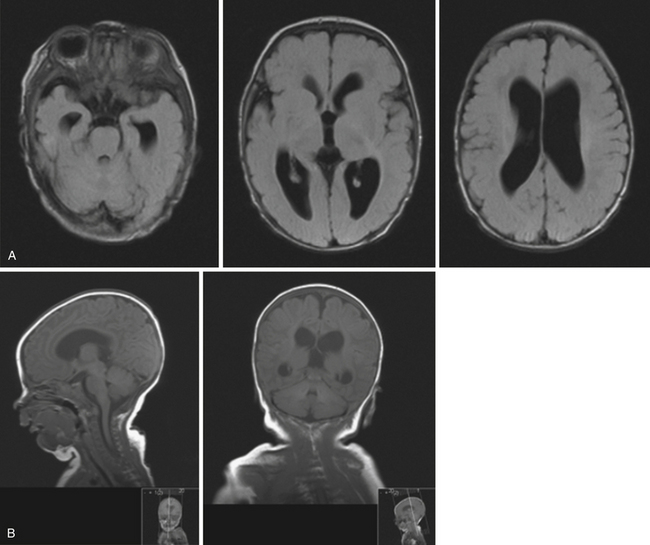

Hydrocephalus in Children and Adults | Neupsy Key

Hydrocephalus in Children and Adults | Neupsy Key

Hydrocephalus in Children and Adults | Neupsy Key

Hydrocephalus in Children and Adults | Neupsy Key